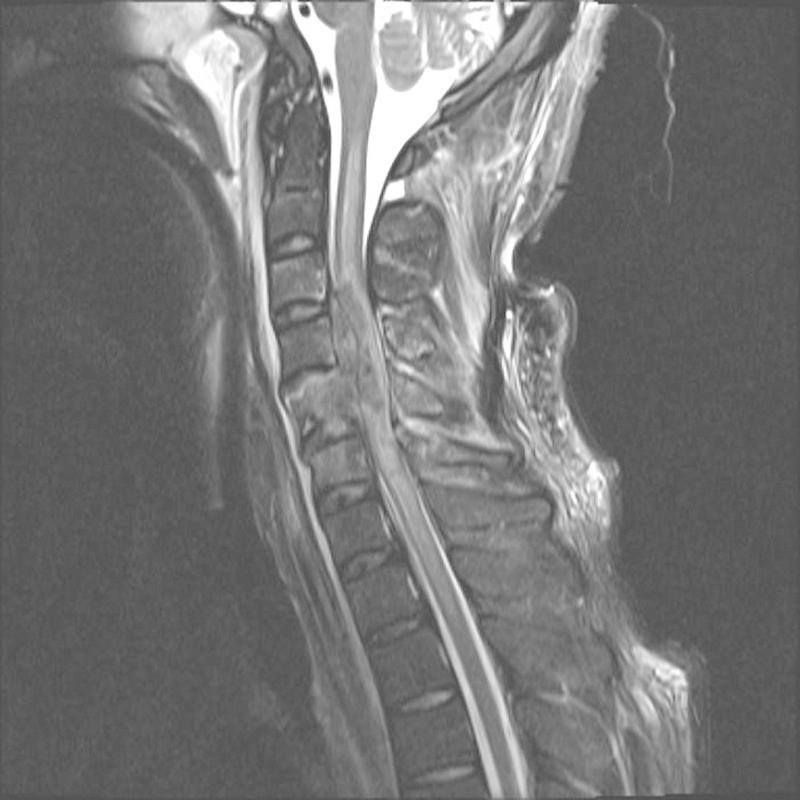

Despite promising advances in basic spinal cord repair research, no effective therapy resulting in major neurological or functional recovery after traumatic spinal cord injury (tSCI) is available to date. The neurological examination according to the International Standards for Neurological and Functional Classification of Spinal Cord Injury Patients (International Standards) has become the cornerstone in the assessment of the severity and level of the injury. Based on parameters from the International Standards, physicians are able to inform patients about the predicted long-term outcomes, including the ability to walk, with high accuracy. In those patients who cannot participate in a reliable physical neurological examination, magnetic resonance imaging and electrophysiological examinations may provide useful diagnostic and prognostic information. As clinical research on this topic continues, the prognostic value of the reviewed diagnostic assessments will become more accurate in the near future. These advances will provide useful information for physicians to counsel tSCI patients and their families during the catastrophic initial phase after the injury.

尽管基础脊髓修复研究取得了令人鼓舞的进展,但迄今为止,尚无有效的治疗方法能在创伤性脊髓损伤(tSCI)后实现主要的神经或功能恢复。根据国际脊髓损伤患者神经和功能分类标准(国际标准)进行的神经学检查已成为评估损伤严重程度和水平的基石。基于国际标准中的参数,医生能够以高精度告知患者有关预期的长期结果,包括行走能力。对于那些无法进行可靠的物理神经学检查的患者,磁共振成像和电生理学检查可能提供有用的诊断和预后信息。随着对该主题的临床研究不断进行,在不久的将来,所审查的诊断评估的预后价值将变得更加准确。这些进展将为医生在损伤后的灾难性初始阶段为 tSCI 患者及其家属提供有用的信息。